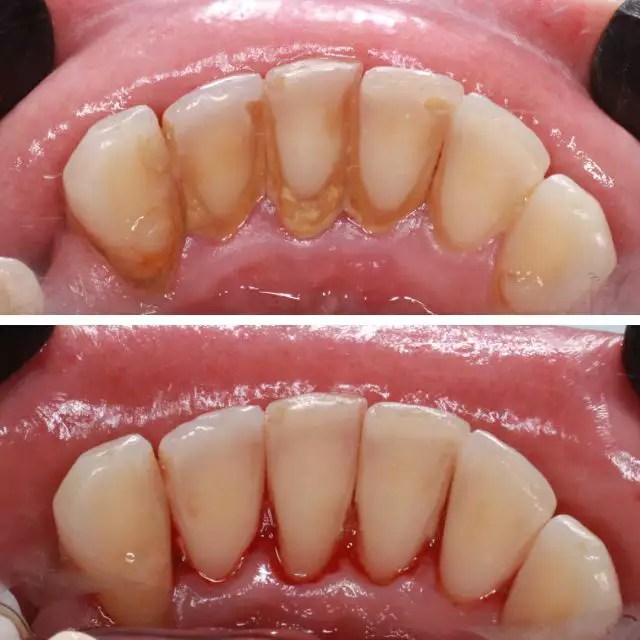

Les interventions chirurgicales comprennent la chirurgie d’accès pour accéder aux zones infectées, les greffes osseuses pour régénérer l’os perdu, le recouvrement radiculaire pour couvrir les racines exposées, l’augmentation du volume gingival pour améliorer l’esthétique, la régénération guidée des tissus pour encourager la croissance cellulaire appropriée, et la chirurgie plastique parodontale pour des fins esthétiques